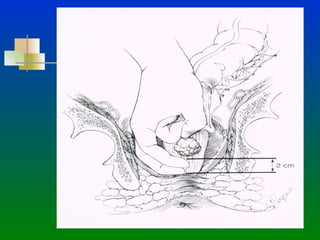

CANCER DE RECTO PRESERVACION DE ESFINTER ANATOMIA: El Recto  se divide en 3 tercios: 1/3 Superior :  Se extiende del promontorio del Sacro  hasta la reflexión  peritoneal. 1/3 Medio:  Inicia en la Reflexión Peritoneal anterior hasta  5-6 cms. del margen anal. (10-11 cms del margen anal) 1/3 Inferior : Inicia a los 5-6 cms. del margen anal y termina  en el esfínter anal.

CANCER DE RECTOPRESERVACION DE ESFINTER ANATOMIA: El Recto se divide en 3 tercios: 1/3 Superior : Se extiende del promontorio del Sacro hasta la reflexión peritoneal. 1/3 Medio: Inicia en la Reflexión Peritoneal anterior hasta 5-6 cms. del margen anal. (10-11 cms del margen anal) 1/3 Inferior : Inicia a los 5-6 cms. del margen anal y termina en el esfínter anal.